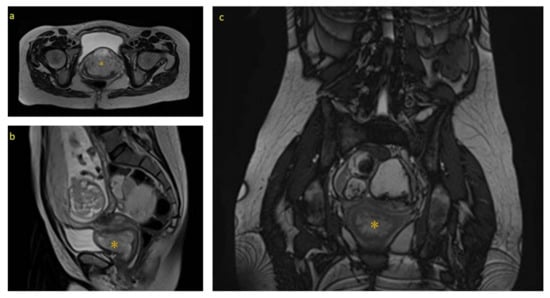

The ultrasound examination at week 20 found fetal findings within normality, with female fetal sex. The previously described tumors were visualized without changes in terms of measurements and ultrasound characteristics. The Doppler of the uterine arteries was pathological, so a follow-up was scheduled at week 26. A magnetic resonance imaging (MRI) of the pelvis was requested which described, in addition to the already known and stable lesions, a complex tumor located in the 7 × 3 × 3.5 cm vesico-vaginal space that suggested the presence of a pedunculated myoma from the cervix as a diagnostic option (Figure 1 and Figure 2).

Figure 1. Ultrasound image of the mass at the prenatal ultrasound at 20 weeks.